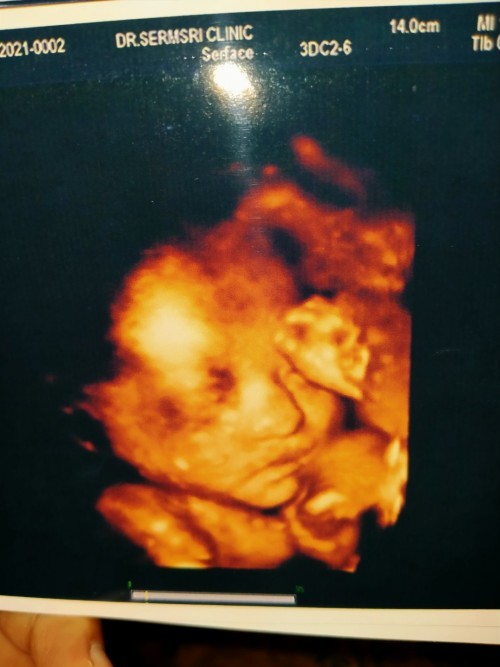

แม่ๆ บ้านไหนคลอด ก.พ.65 เอาภาพมาแบ่งกันดูหน่อยค่ะ ตื่นเต้นอยากให้ถึงวันนั้นเร็วๆมากค่ะ 18 ก.พ.65😍😍#ท้องแรกคะ